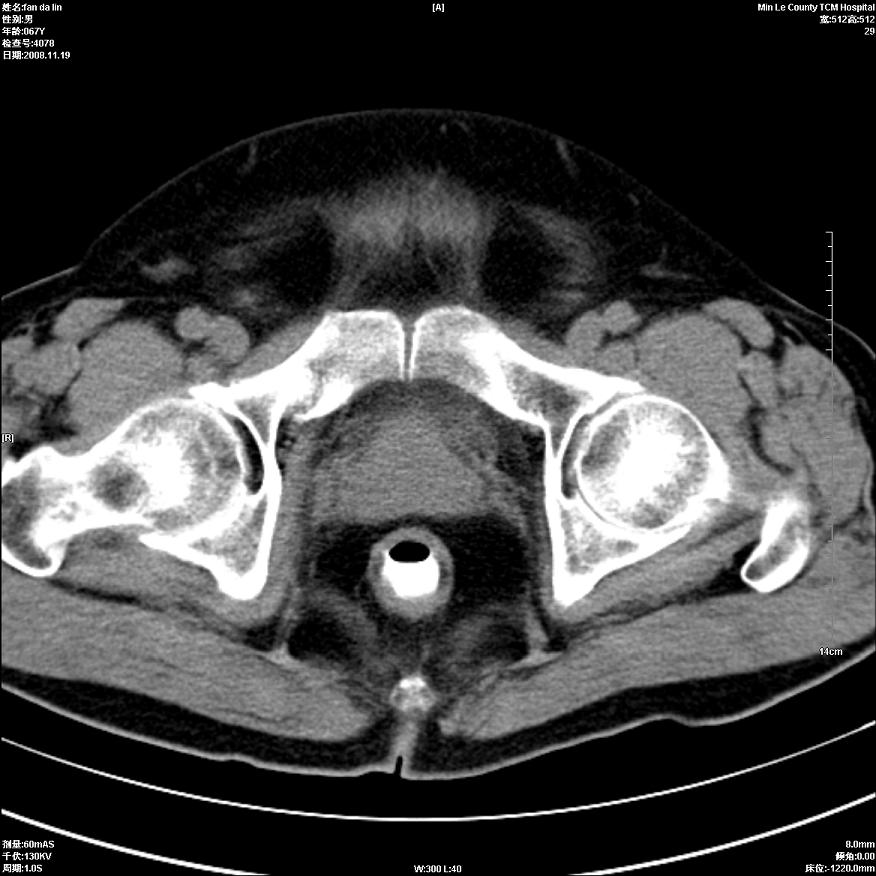

标题: CT16698:M67Y,看看直肠下端是不是病变 [打印本页]

标题: CT16698:M67Y,看看直肠下端是不是病变

粘膜皱壁,不除外内痔

直肠及乙状结肠管壁均增厚,考虑炎症.

直乙交界处肠壁不规则增厚,还是做个肠镜吧

只是肠壁局限性增厚,但难说明问题。